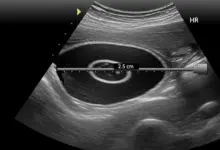

- A ressonância magnética identifica lesões labrais, capsulares e tendíneas.

- A tomografia é solicitada quando há suspeita de defeitos ósseos relevantes.

Essas informações permitem escolher a técnica adequada e prever o risco de falha do tratamento conservador.